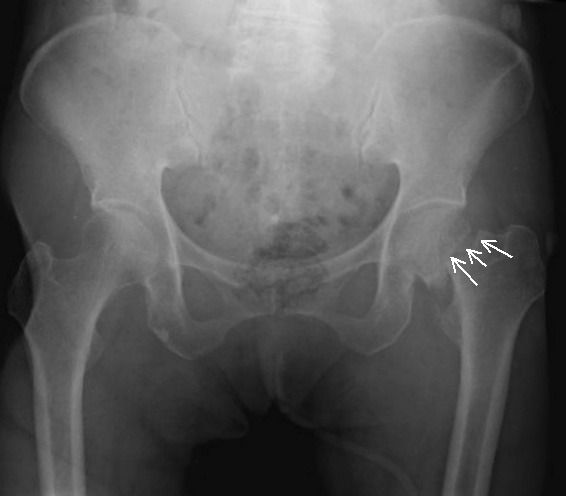

その後病院にいき、骨折が判明しました。